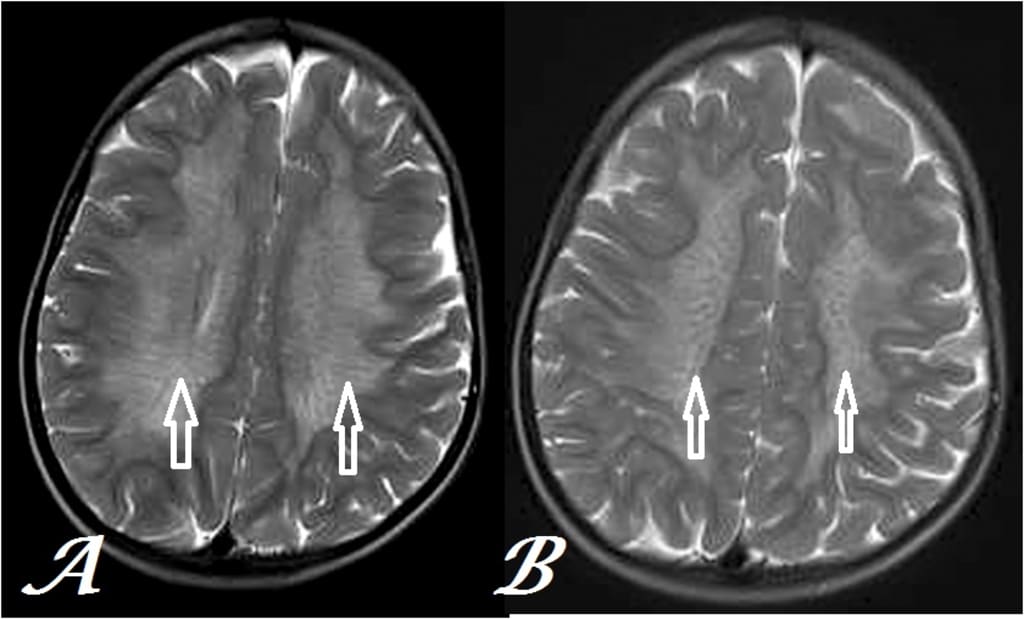

Metachromatic leukodystrophy represents a rare genetic disorder characterized by the accumulation of fatty substances in cells, particularly in the spinal cord, brain, and peripheral nerves. This buildup is due to a deficiency of an enzyme called sulfatides, which aid in breaking down lipids. Based on the age at which symptoms manifest, metachromatic leukodystrophy is of three types: the late infantile form, the juvenile form, and the adult form.